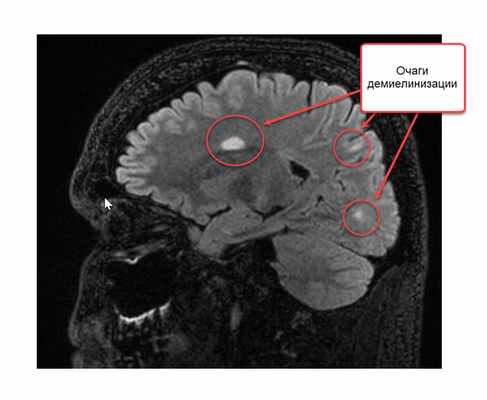

Признаки рассеянного склероза на МРТ головного мозга манифестируют себя следующим образом:

- появлением новых очагов и увеличением старых;

- во время обострения проведение МРТ головы с контрастом будет приводить к тому, что очаги демиелинизации будут накапливать контраст причудливым кольцевым способом.

Как распознают рассеянный синдром на снимках? При рассеянном склерозе на снимках заметно характерно типичное распределение очагов в белом веществе головного мозга. Кроме того, для данного диагноза характерно поражение мозолистого тела, дугообразных волокон, височных долей, мозгового ствола, мозжечка и спинного мозга. Такое распределение очагов нехарактерно для иных патологических процессов, поэтому трудностей при постановке диагноза обычно не возникает. При ангиопатии возможны поражения ствола мозга, однако они обычно симметричны и располагаются центрально, в то время как очаги при рассеянном склерозе локализованы по периферии.

В методе магнитно-резонансной томографии, исходя из названия, применяется иная физическая основа. Кратко опишем этот метод. Итак, из школьного курса физики мы знаем, что существует магнитное поле. Оно есть у всех тел в природе: у нашей Земли, у нашего с Вами тела, у каждого атома нашего тела. Поэтому к каждому телу можно пририсовать стрелку, показывающую направление магнитного поля. Если к атому прилагается внешнее магнитное поле, более сильное, чем у атома, то магнитное поле атома стремится выстроиться вдоль внешнего магнитного поля, параллельно ему. Насколько быстро и насколько точно встанет стрелка магнитного поля атома зависит от свойств самого атома: одни атомы выстраиваются быстро и ровно по направлению внешнего поля, другие с отклонением и медленно. В магнитно-резонансном томографе подается мощнейшее магнитное поле, чаще всего его напряженность составляет 1,5 Тл. К примеру, магнитное поле всей Земли составляет 0,00005 Тл. Магнитно-резонансный томограф представляет собой очень большой магнит, в центре которого напряженность магнитного поля наибольшая. Вас кладут на кушетку, затем кушетка начинает двигаться к центру магнита, похожего на трубу. Когда Вы достигаете центра магнита, то начинается процесс исследования. Магнитные поля всех атомов Вашего тела выстраиваются вдоль поля большого магнита (все маленькие стрелки встают параллельно большой стрелке). Затем перепендикулярно к основному полю магнита подается кратковременный импульс другого сильного поля. Это приводит к наклону всех маленьких стрелок атомов Вашего тела – они выстраиваются уже вдоль этого кратковременного, но очень сильного магнитного поля. Грубо говоря, все магнитные оси атомов ложатся на бок. Когда действие импульса заканчивается, магнитные стрелки атомов вновь возвращаются в положение вдоль направления магнитного поля основного магнита (вдоль трубы). Так вот, скорость возврата магнитных осей из положения на боку в вертикальное положение у разных атомов различно. У атомов водорода оно одно, у атомов кислорода другое, у атомов меди третье, у атомов железа четвертое. А так как каждый участок тела, каждый участок головного мозга состоит из разного количества разных атомов, то и возврат атомов к вертикальному положению осей будет от каждого микроскопического участка головного мозга разным. Существует два основных вида изображений: T1-взвешенное и T2-взвешенное. На Т1-взвешенном изображении фиксируется скорость возврата атомов из положения на боку в вертикальное положение. На Т2-взвешенном изображении время удержания атомов в положении на боку после кратковременного перпендикулярного импульса. Компьютерная программа обрабатывает микроскопические участки мозга по этим параметрам и формирует изображение. Участки демиелинизации существенно отличаются по количеству и спектру атомов от здоровой ткани и видны на Т2-взвешенном изображении в виде белых очагов.

Следует упомянуть и про режим FLAIR: построение изображения в этом режиме происходит путем удаления (не учета) молекул воды, что дает более четкую и более полную картину очагов демиелинизации.